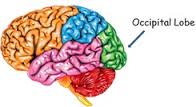

Occipital Lobes

This region includes the primary visual cortex and the visual association areas of the brain. Injury to the occipital lobes may lead to vision impairments such as blindness or blind spots; visual distortions and visual inattention. The occipital lobes are also associated with various behaviors and functions that include: visual recognition; visual attention; and spatial analysis.

This region includes the primary visual cortex and the visual association areas of the brain. Injury to the occipital lobes may lead to vision impairments such as blindness or blind spots; visual distortions and visual inattention. The occipital lobes are also associated with various behaviors and functions that include: visual recognition; visual attention; and spatial analysis.